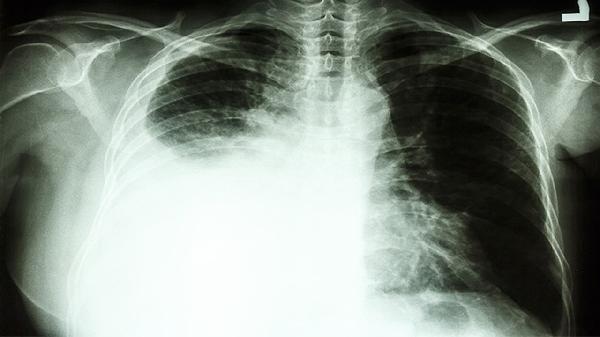

肺癌在进展期可能转移至骨骼或侵犯臂丛神经,导致持续性左肩膀痛,常伴有咳嗽、体重下降等全身症状,这种情况较为少见但需高度警惕。其他肿瘤如乳腺癌转移也可能引起类似症状,但概率较低,需结合影像学检查确诊。

如果左肩膀痛持续不缓解或伴有其他警示症状如咯血、呼吸困难,建议及时就医进行胸部CT等检查,以排除肺癌等严重疾病,同时注意保持健康生活方式,避免吸烟和接触有害物质,定期体检有助于早期发现潜在问题。